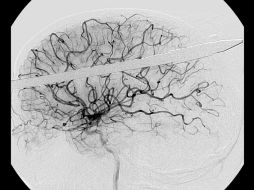

Tecnología Atacan la epilepsia con impulsos eléctricos 23 de mayo de 2013 - 19:08 hs Ciencia médica Epilepsia